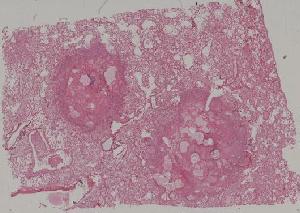

41. Opportunistic infection in the lung